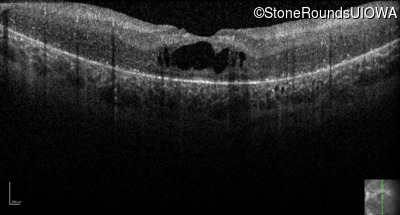

Optical Coherence Tomography - Right - 20/80 -1

Exemplar / OCT Stack

OCT Stack